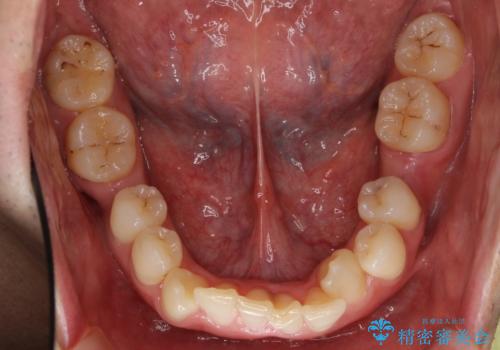

八重歯の矯正+歯のないところにインプラント

- 八重歯を主訴に来院。

下の歯がないところに、奥歯が倒れこんでいたため、矯正治療で倒れこんだ歯を起こして、インプラントを植立しました。

上の前歯が下の前歯に大きく重なっており、過蓋咬合を呈していました。

上顎の小臼歯2本、下顎の親知らずを抜歯しています。